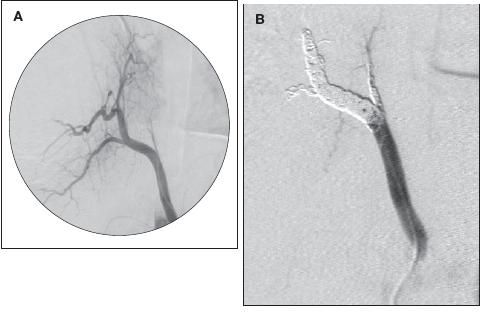

A CT scan of the chest showed a right hemothorax, a lower lobe mass that extended to the middle lobe, cystic areas surrounding the mass, and what appeared to be a vessel coming off the descending aorta adjacent to the celiac axis and feeding into the mass (Figure 2). After bronchoscopy failed to control the bleeding, urgent aortic angiography with subsequent embolization of the feeding artery was performed, and the crisis abated (Figure 3).

Figure 3 – An aortic angiogram shows the feeding artery to the sequestration (A) and subsequent embolization of the feeding artery (B).